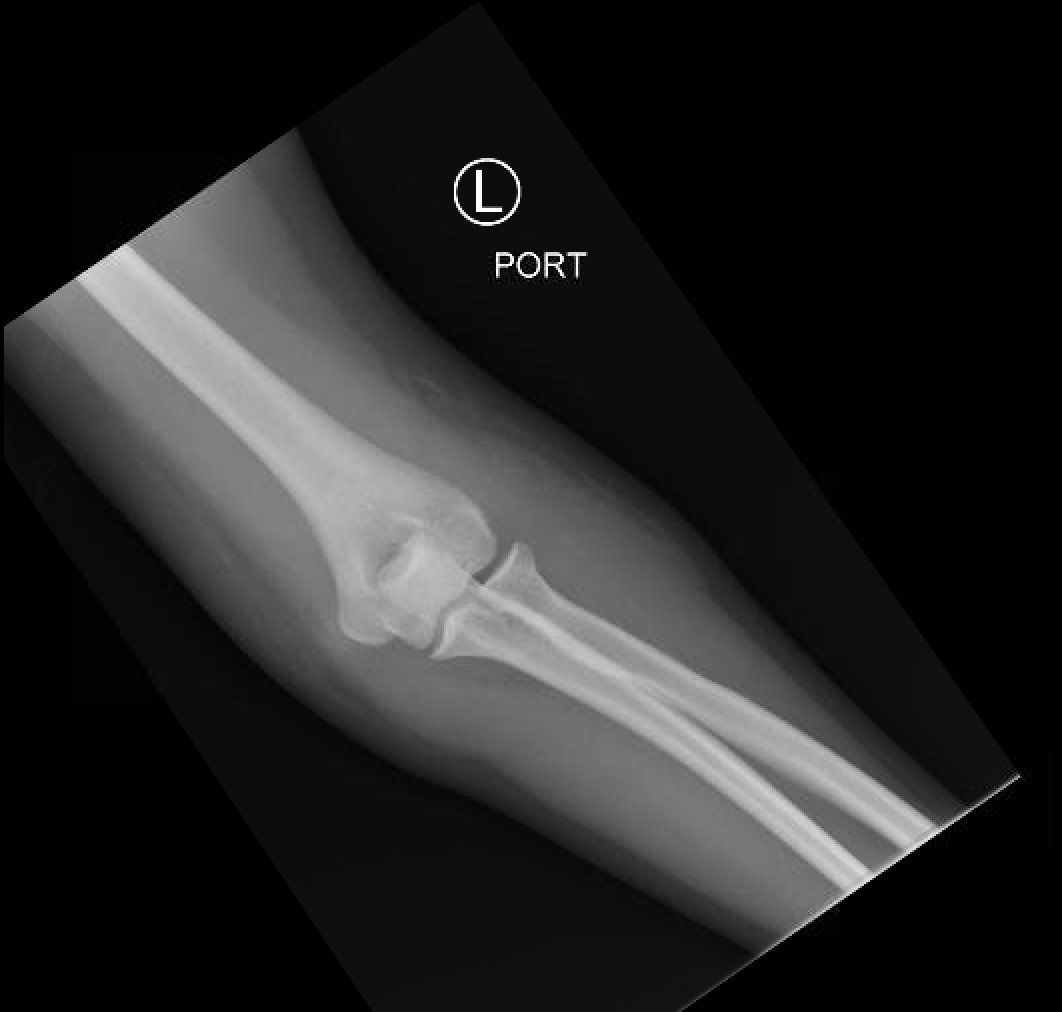

Posterior Elbow Dislocation, AP XRay, reduced. JETem 2016

Posterior Elbow Dislocation